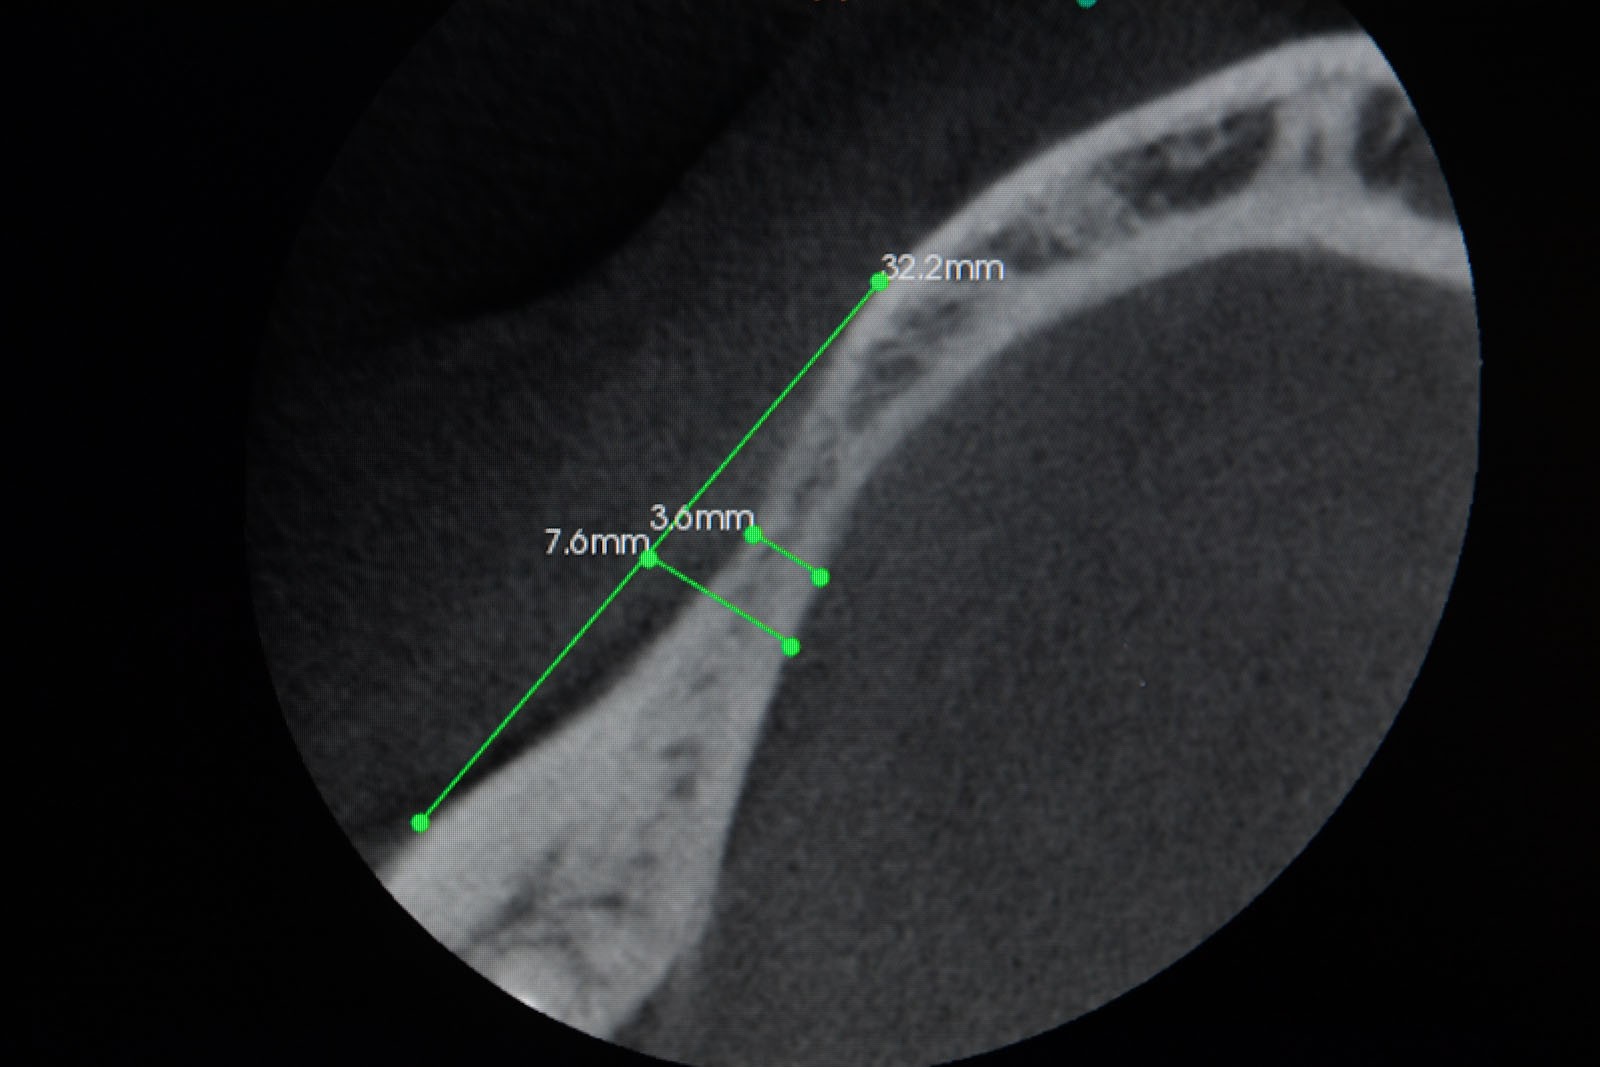

Przed podjęciem leczenia należy określić stopień zaniku kości szczęk oraz żuchwy. W tym celu przeprowadza się badanie kliniczne oraz odpowiednią diagnostykę obrazową pacjenta. Uwzględnia ona zdjęcie panoramiczne OPG jako podstawę dwuwymiarowego obrazowania podłoża kostnego oraz możliwe jest badanie tomograficzne CT lub bardziej precyzyjna tomografia stożkowa CBCT. Opcjonalnie wykorzystywana diagnostycznie tomografia pozwala na bardziej wnikliwą ocenę stopnia zaniku kości w trójwymiarowym, przestrzennym obrazie.

Precyzja projektu druku siatki bazuje na dokładności odwzorowania kształtu kości w stożkowej tomografii komputerowej CBCT, co zapewnia ich dobre przyleganie do podłoża kostnego oraz ogranicza powstawanie powikłań w postaci obnażania się siatek.